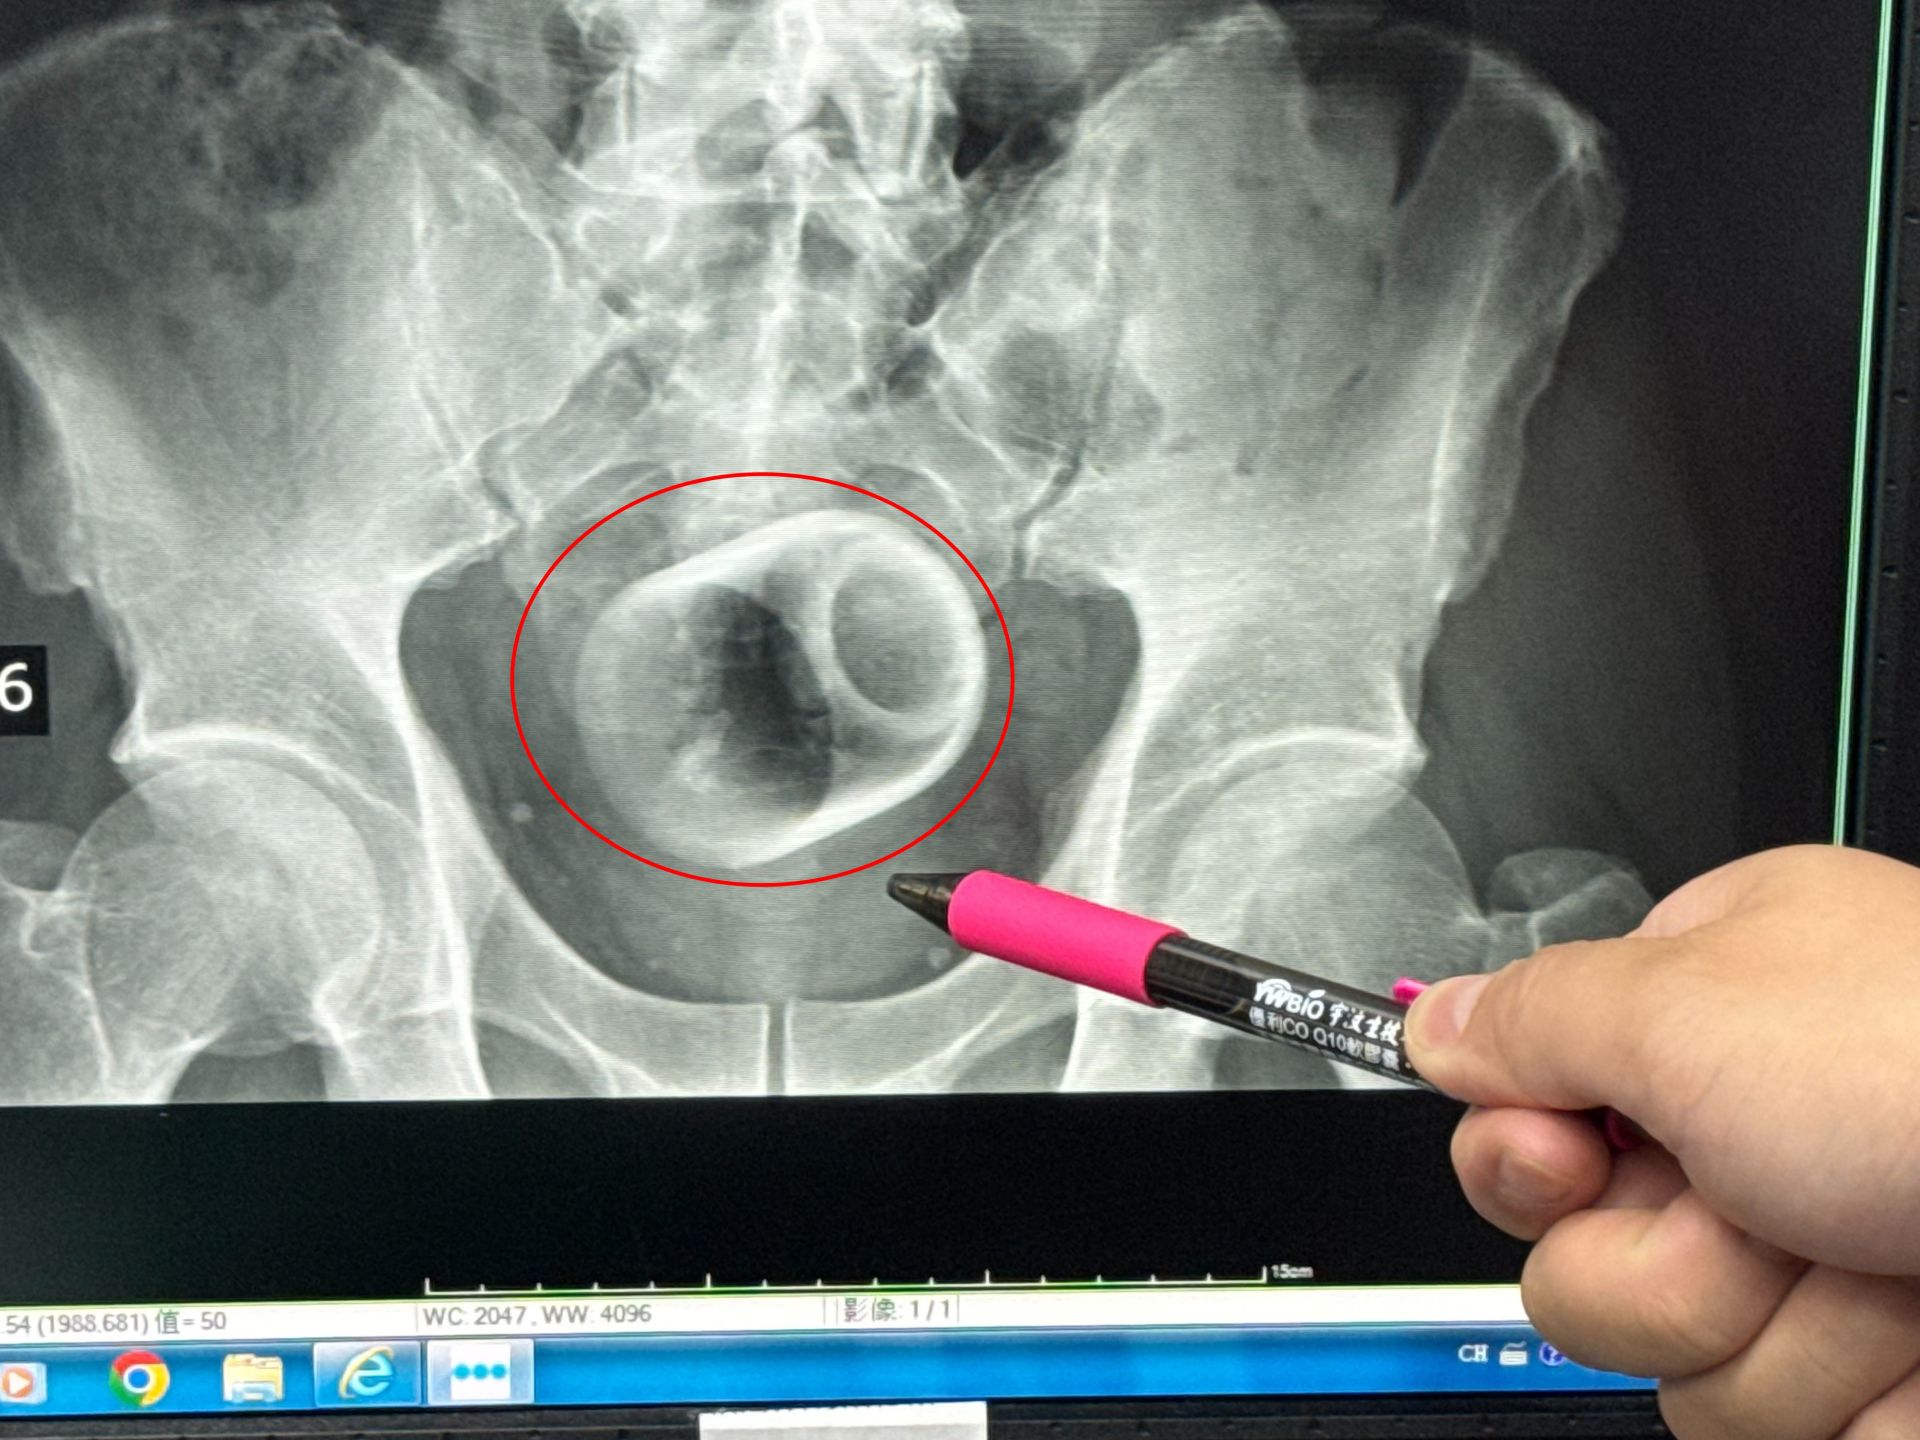

一名男子把陶瓷杯塞進肛門,X光片顯示出杯子放在骨盆腔內,經手術後才取出。大甲李綜合醫院提供

【Lai傳媒 記者爆料網 蔡智銘/台中報導】中部一名男子腹脹三天無法大便,肚子痛到受不了,趕緊到醫院求診,經過X光檢查,醫師驚見患者的肛門竟然塞一個直徑約6公分、高約8公分的陶瓷杯,外科醫師原本要使用器械把杯子夾出來,但杯緣光滑無法施力,杯子全被大腸包住,部分腸子缺血也造成壞死,最後全身麻醉「開腸破肚」的才把杯子取出。

駐診在李綜合醫院的台中榮總外科醫師吳坤達表示,該名患者到院時,自訴三天無法大便非常困擾,害羞不敢提及自己肛門塞了一個杯子,經過X光攝影,看到骨盆腔內有一個杯子,杯口朝下,因此,馬上安排進手術室,要把杯子拿出來。

吳坤達說,一開始試著使用器械直接把杯子夾出來,但是杯子光滑,用了很多器械,試了很多次都無法成功,後來再使用腹腔鏡,依舊無法順利取出,擔心把杯子夾碎,傷及患者或造成感染風險,最後只好在肚子上動刀,直接「破肚開腸」劃開腸子,總共花了兩個多小時,才順利取出杯子,同時做了一個人工造口,讓患者能夠暫時解便。